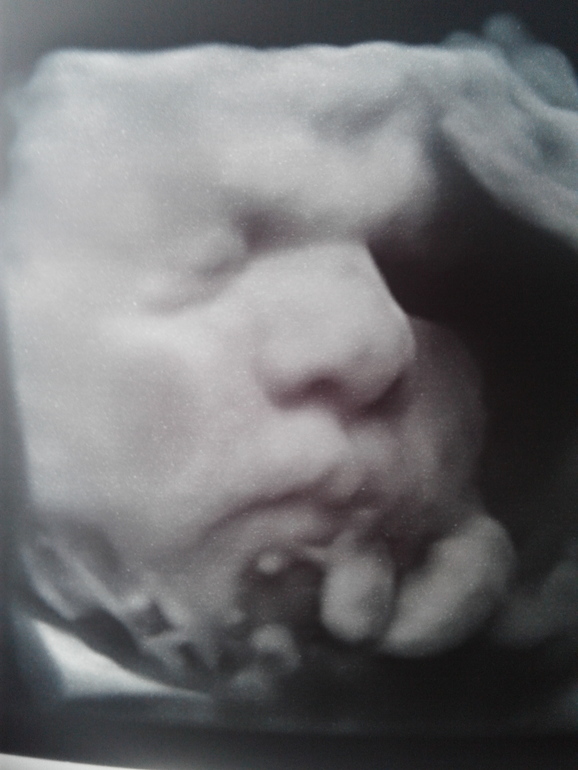

Шёл 10-ый месяц моей Б...

Личико малыша на мальчика похоже )

Какой щекастый :) пора уже на выход а то потом щеки не пролезут 😂😂😂

Животик на пацана похож)))

Почему то посмотрев фото подумала что парень)))) Легких родов

Кстати я тоже так подумала)

серьезный бутуз!!!легких вам родов!